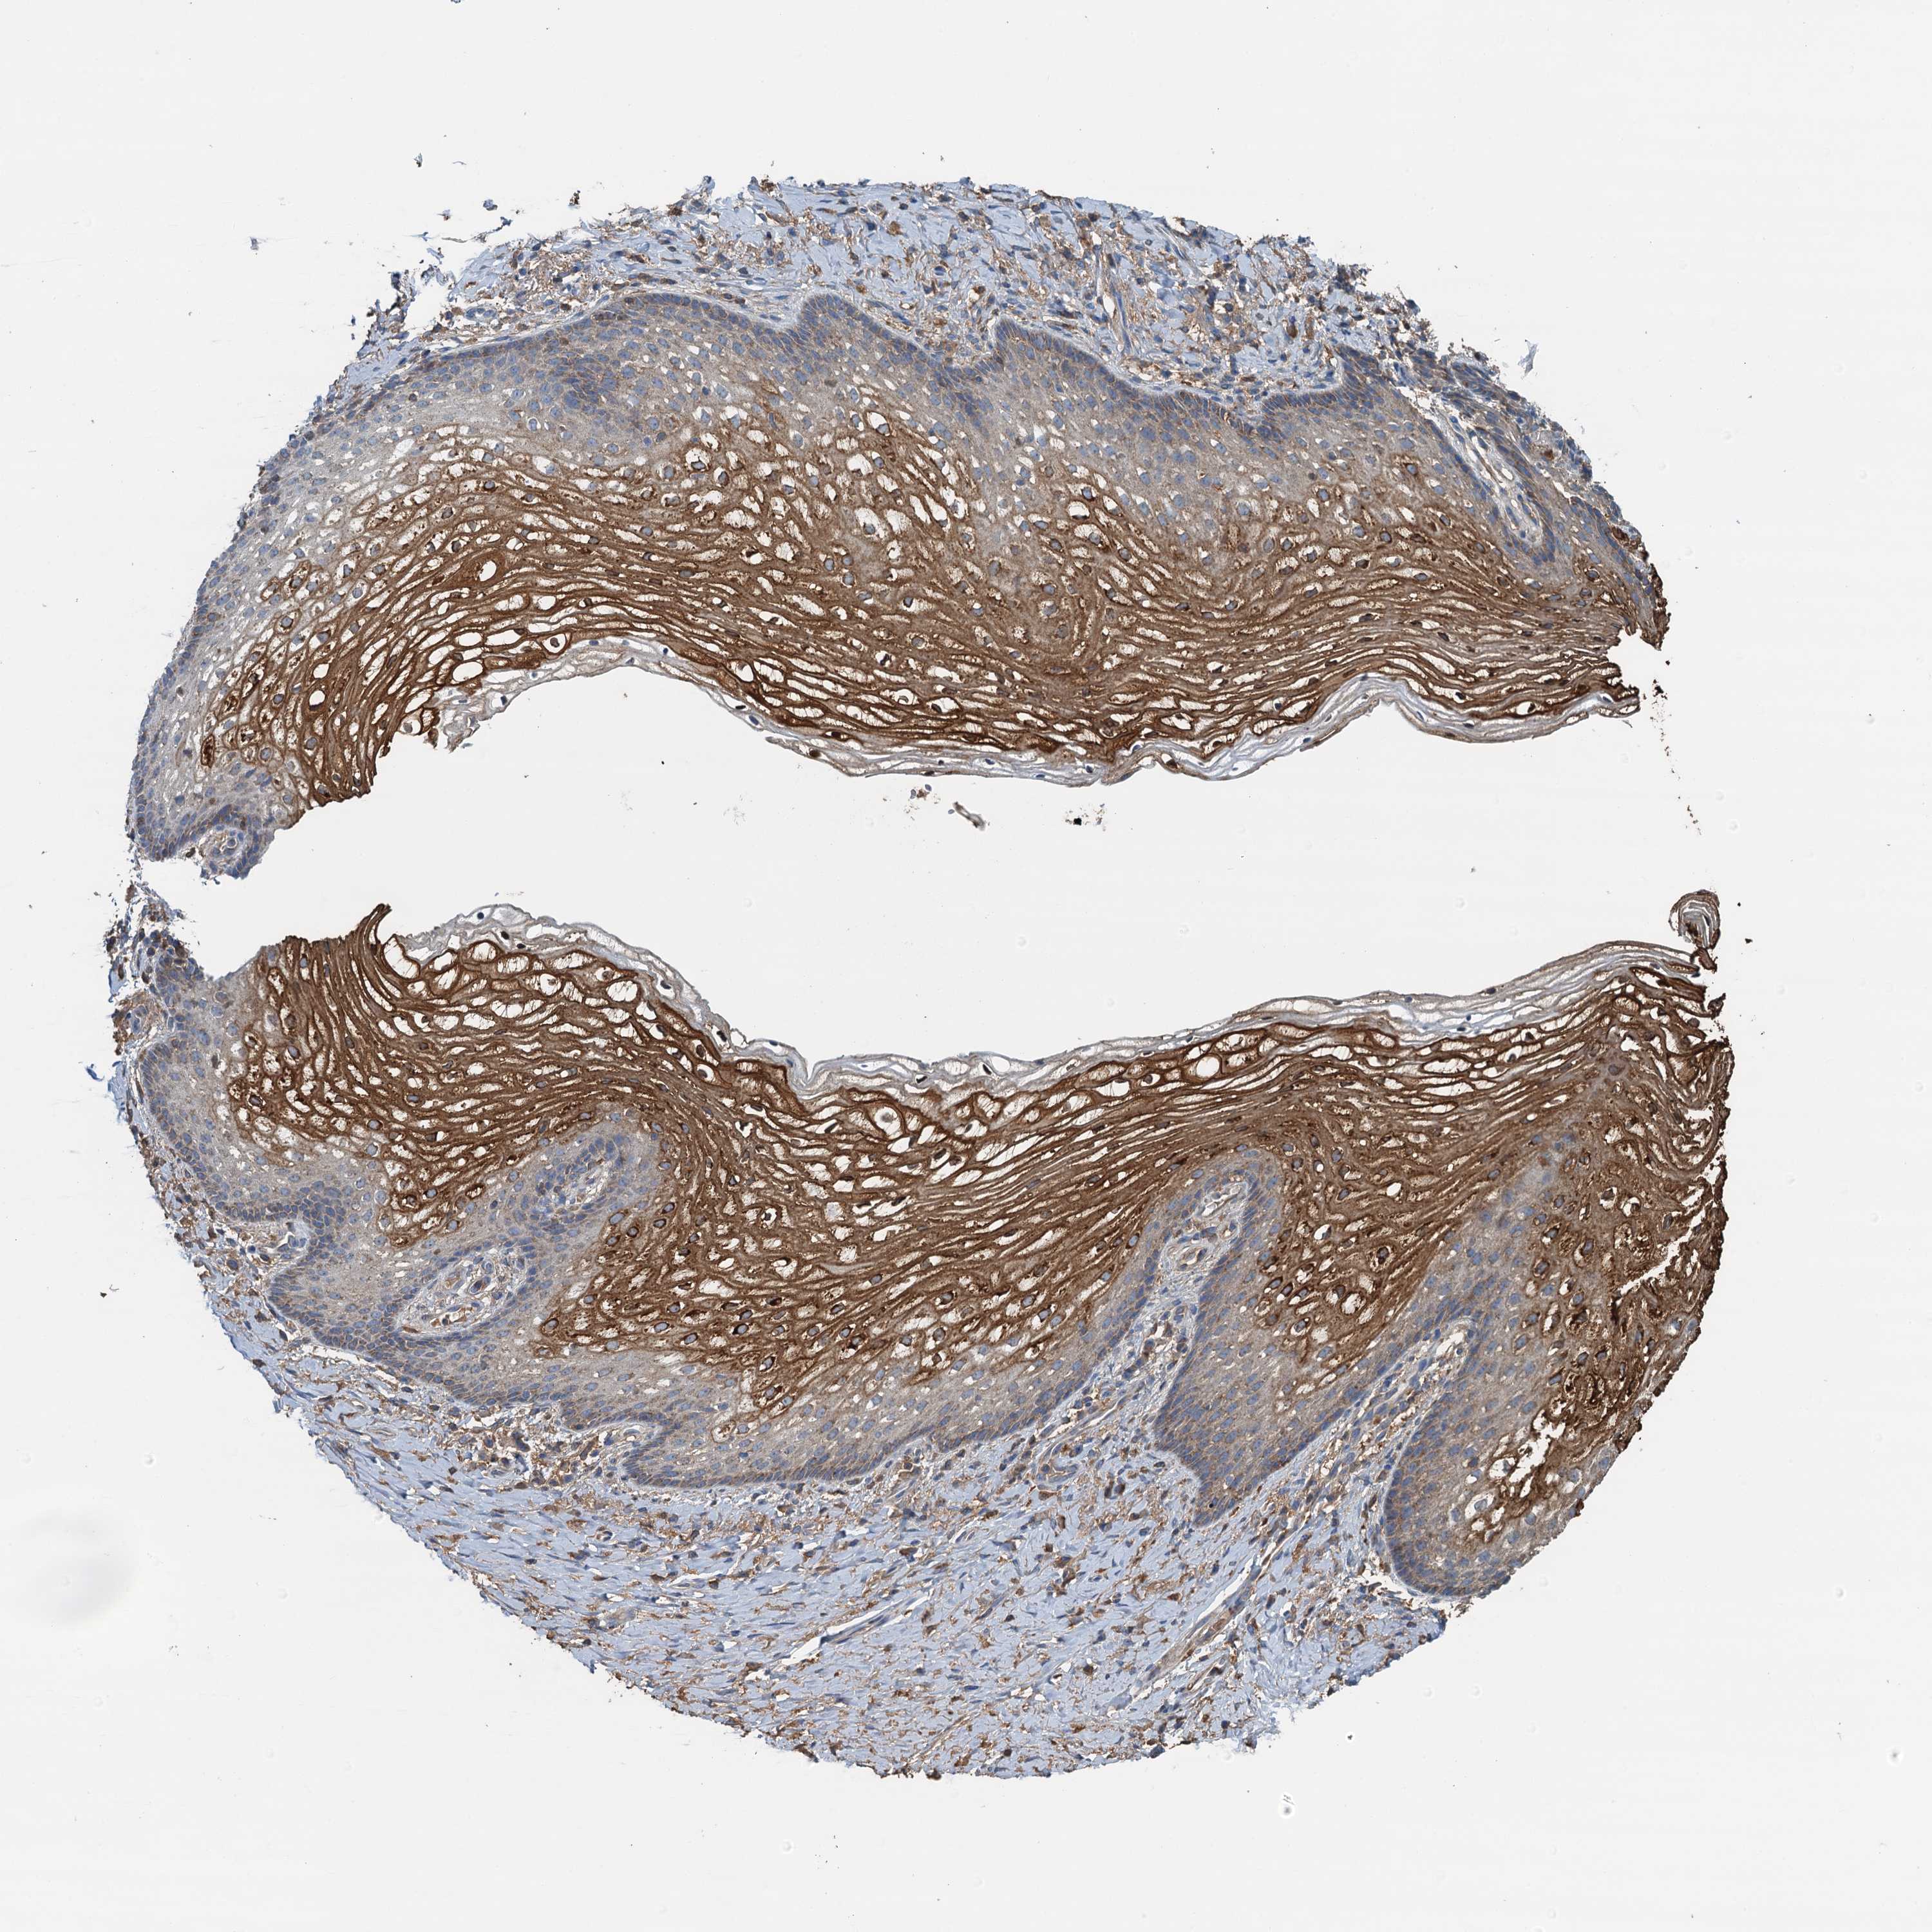

Antibody staining in the annotated cell types in the current human tissue is reported as not detected, low, medium, or high. This score is based on the staining intensity and fraction of stained cells.